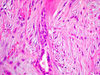

CASO N° 1 (Dr. Jair e Dr. Delgado)

Paciente do gênero masculino, 44 anos de idade, apresenta uma lesão no palato duro e palato mole.